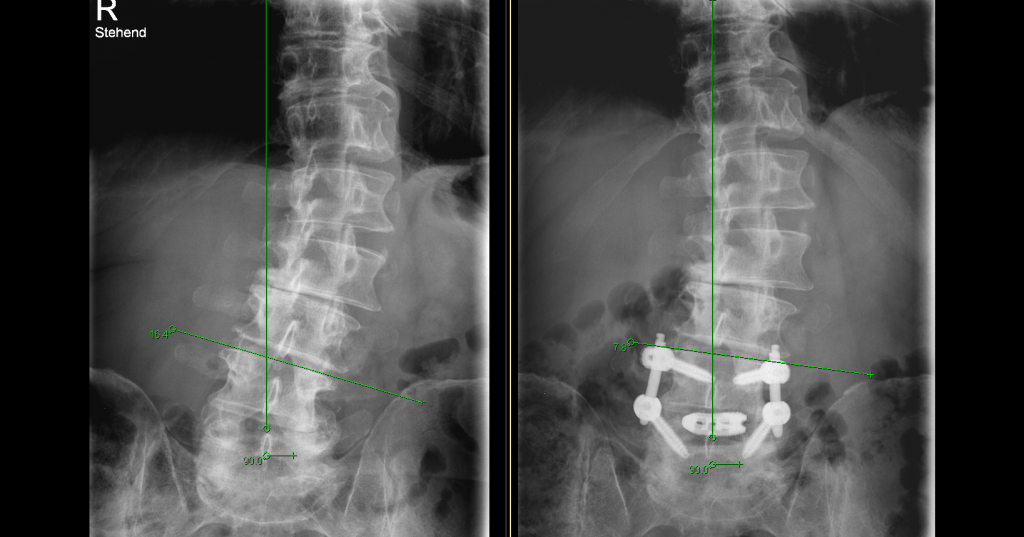

Wenn wir älter werden, nehmen die Verschleisserkrankungen zu. Und die Wirbelsäule verliert oft die gerade, aufrechte Struktur und wird krumm und krümmer. Im Röntgenbild sehen wir oft ganz verschiedene Verschleisssituationen nebeneinander. Da die Wirbelsäule aus verschiedenen Bewegungssegmenten besteht, muss der Wirbelsäulenchirurg genau wissen, woher der Schmerz kommt. Würde man sich…